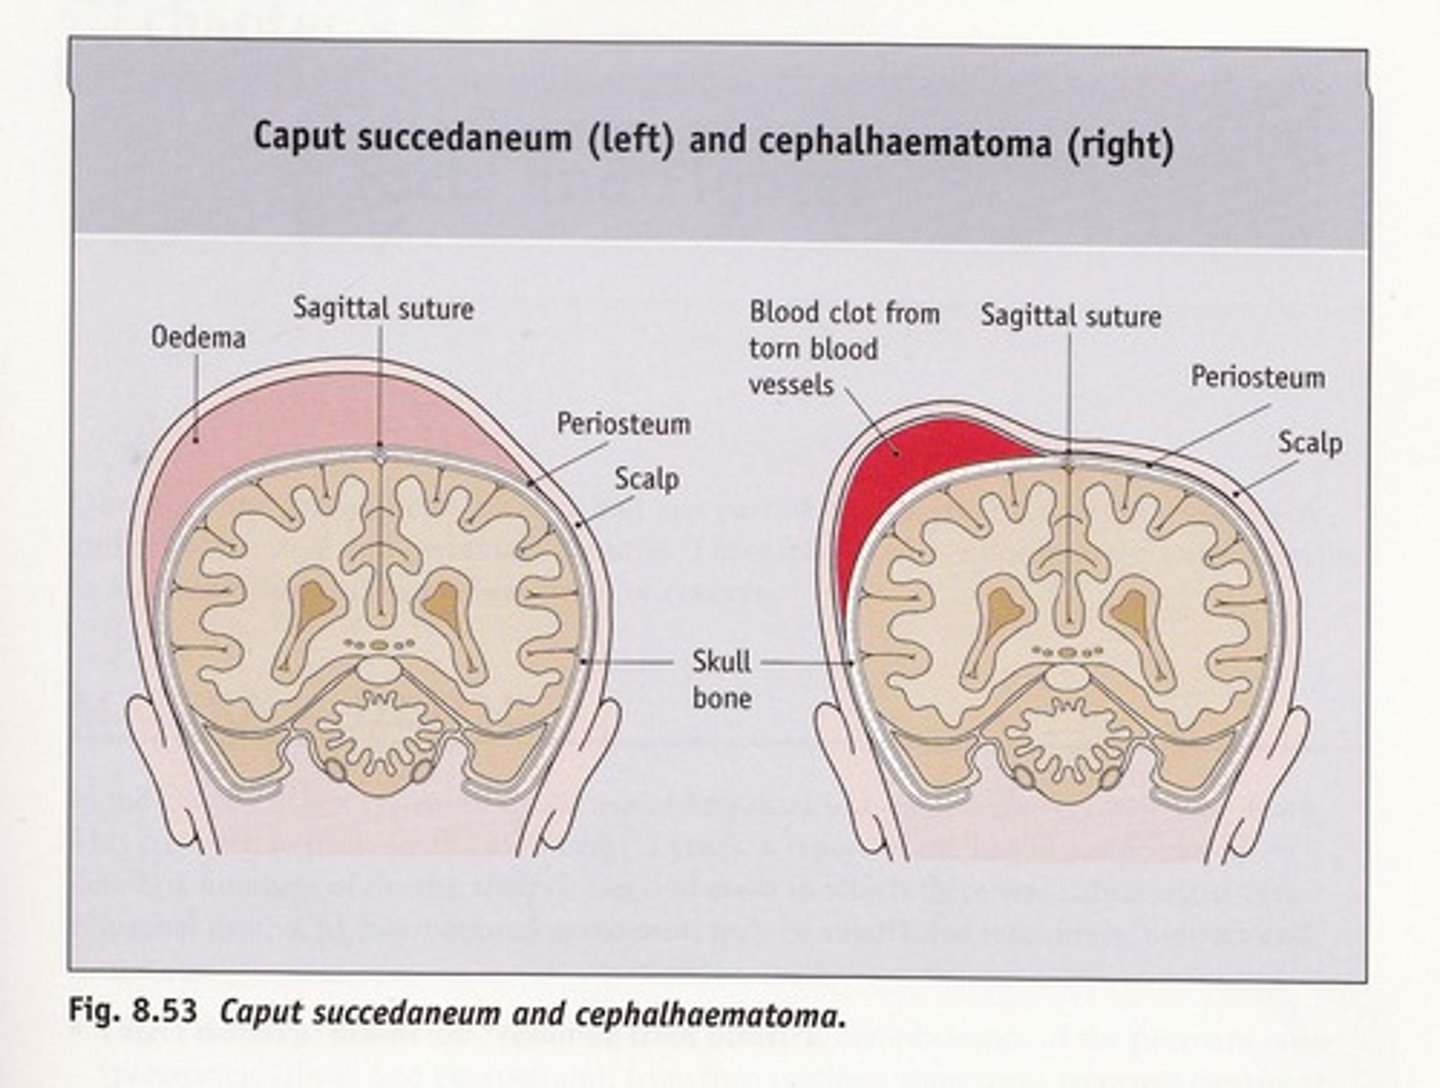

What head abnormality is characterized by superior edema/ecchymosis that crosses the suture lines

Caput succedaneum

Cephalohematoma does NOT cross the suture line